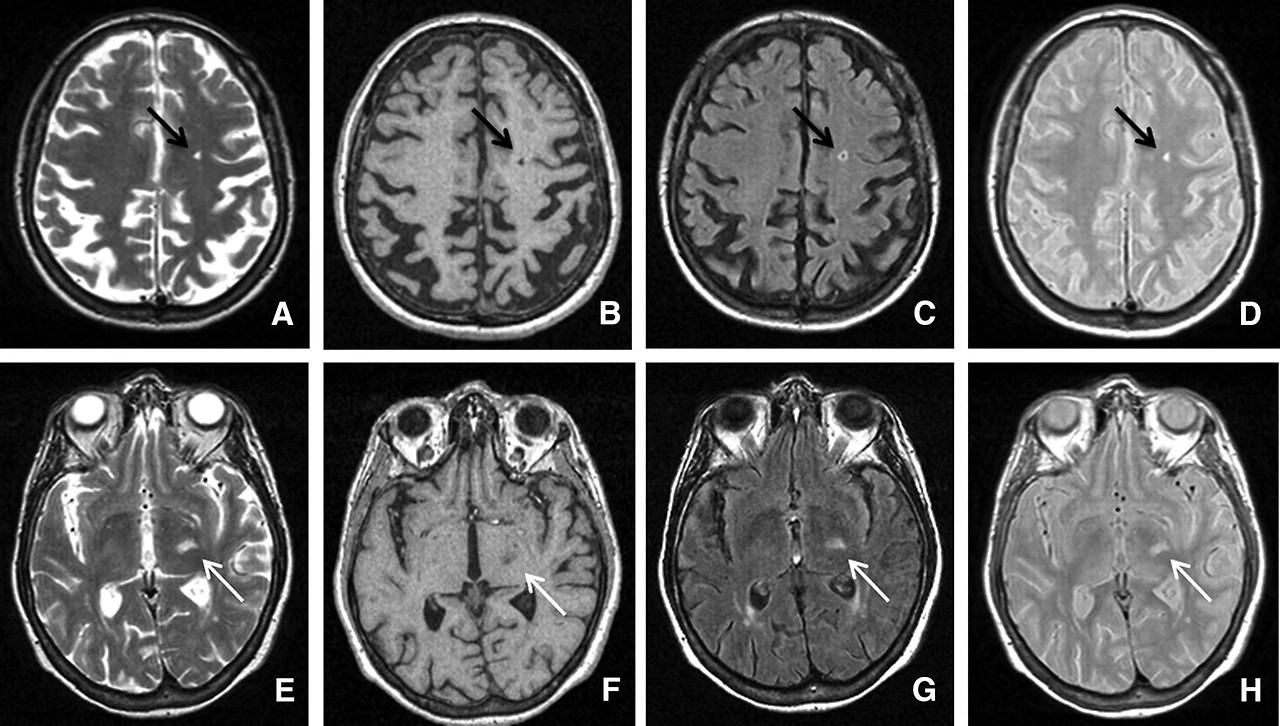

이런 MR 이상 소견은 크기와 위치, MR 신호 강도에 따라 만성 뇌 허혈 변화, 미세 출혈, 무증상 뇌경색 의심 소견, 무증상 뇌경색으로 판독할 수 있는데요, MRI 진단 기준에 대해서도 학계에서 계속 업데이트 중입니다. 뇌척수액이 있는 빈 공간(Virchow-Robin Spaces)은 무증상 뇌경색과 매우 닮은꼴을 하는 경우도 있습니다.

<Silent Brain infarcts, Stroke Volume 42, Issue 4, April 2011>에 수록된 영상 이미지

MRI 소견 하나로 정답이 나오는 게 아니라, 판독 결과와 임상 소견을 종합하여 앞으로의 치료와 추적 관찰 계획을 정합니다.